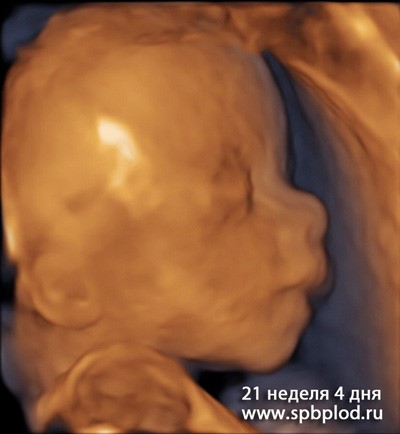

УЗИ пплода в 21 неделю и 4 дня в режиме 3D

В 18-22 недели беременности плод достигает массы 400-500 грамм и длины 22-27 см. При таких размерах ультразвуковое исследование позволяет детально рассмотреть все анатомические структуры плода и выявить большинство пороков развития, которые требуют хирургической коррекции или приводят к ухудшению качества жизни ребенка. Кроме того, на этом УЗИ проводится поиск маркеров (признаков) болезни Дауна и других хромосомных болезней. Вид многих органов плода при болезни Дауна имеет небольшие отличия от вида нормальных органов, и комплексная оценка всех анатомических структур позволяет оценить риск наличия у плода болезни Дауна и рекомендовать, при необходимости, углубленную диагностику (инвазивными методами) этого заболевания.